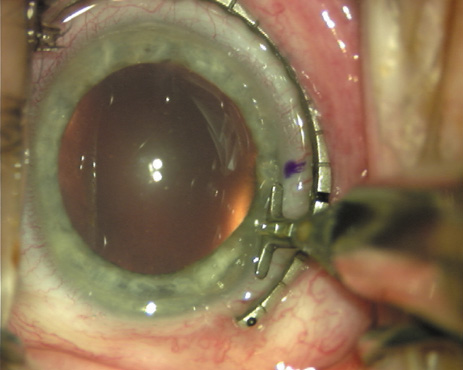

Case 3 is a 48-year-old bilateral hyperope who presented for a refractive surgical consultation. The refraction in his left eye was found to be +3.25 +1.75 × 85. Keratometry was somewhat flat but confirmed WTR cylinder as did corneal topography. Based upon the patient's age, refraction, and somewhat shallow anterior chambers, the decision was made to proceed with a refractive lens exchange. The NAPA nomogram called for LRIs of 55 to 60 degrees with intraoperative pachymetry. Intraoperative keratoscopy confirmed the steep 85-degree meridian (Figs. 2029).

Fig. 28. 6A side-port incision is created for the surgeon's non-dominant right hand, taking care not to intersect the LRI.

Fig. 29. The single-plane RLE incision is completed.